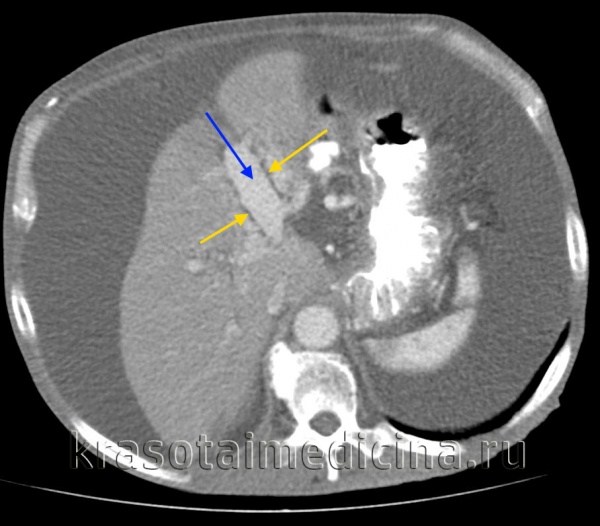

КТ ОБП. Этот же пациент, расширенный левый долевой ствол воротной вены (синяя стрелка) с периваскулярным отеком (желтая стрелка).

КТ ОБП. Этот же пациент, варикозно расширенные вены как проявление синдрома портальной гипертензии (коричневая стрелка).